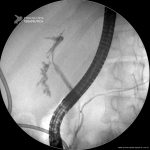

Fístula Biliar

- Imagem da radioscopia mostrando fístula biliar pós-colecistectomia, com identificação de extravazamento de contraste na região do hepatocolédoco médio-proximal.